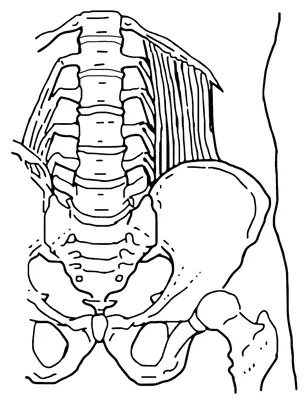

Дорсалгия – боль в спине. Происхождение разное. Чаще всего это мышечная боль, иногда в связках, укрепляющих позвоночник. Далеко не всегда невралгическая, как принято считать, то есть связанная с воспалением нерва, но бывает и так. Главная причина возникновения боли – резкое движение или подъем тяжести. Движение приводит к растяжению мышц и связок, подъем тяжести – к критической нагрузке на позвоночник и диски, которые при этом могут разорвать окружающее их сухожильное кольцо и выдавить гелевое содержимое наружу к расположенным рядом корешкам спинного нерва. Если гелевое выпячивание (его ошибочно называют спинномозговой грыжей) давит на нерв, тот воспаляется, отекает, и возникает сильная боль или онемение в той части тела, которая контролируется этими нервами.

Поясничные мышцы могут растягиваться и повреждаться при резком наклоне или разгибании, тяжелой работе связанной с наклонами, подъемом или переноской тяжести.